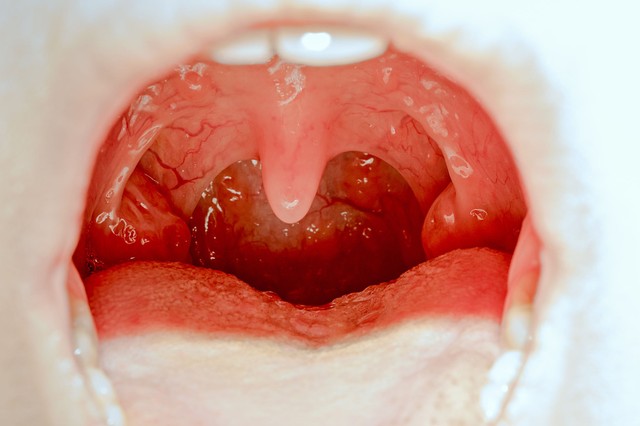

Torokgyulladás

Apró fehér foltokat vett észre a manduláján? Ilyen, amikor mandulakő okozza

A mandulakő legjellemzőbb tünete a rossz lehelet.